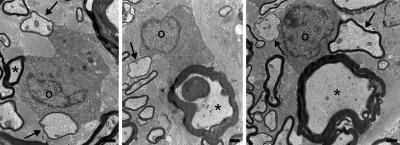

In the new study, the researchers looked at the cats' nervous tissue and found a unique myelin mosaic -- axons surrounded by thick layers of myelin (formed during development when the axons themselves grew) were interspersed with other axons surrounded by thin layers of myelin.

"The most likely explanation of that mosaic appearance is surviving oligos," Duncan says. "Thick myelin sheaths are never seen following remyelination, just thin sheaths. And surviving adult oligodendrocytes are adjacent to these sites of demyelination, making them likely candidates for myelin repair."

Sure enough, the researchers found oligodendrocytes connected to both thick and thin myelin sheaths in the cat spinal cord.

The UW-Madison researchers enlisted Grahame Kidd and the private research lab Renovo Neural in Cleveland to reconstruct stacks of electron microscope images of cat nerve cells into 3D representations that show oligodendrocytes reaching up and down the spinal cord, sustaining mature myelin and remyelinating damaged sheaths.